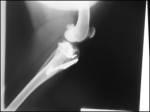

Das Kniegelenk (lat. Articulatio genus) ist das Verbindungsgelenk zwischen Ober-(Femur), Unterschenkel (Tibia) und Kniescheibe (Patella) am Hinterbein.

Durch Muskelverspannungen und Abwehrbewegungen kann die Diagnose schwierig sein. Um andere Ursachen auszuschließen, sollte man ein Röntgenbild der knöchernen Strukturen des Knies anfertigen lassen.

Abbildung: Das Kniegelenk des Hundes (aus "Fossum: Small Animal Surgery", Mosby Verlag, 1997): Ansicht von vorne.

In der Mitte sind das vordere (Cranial cruciate ligament) und das hintere (Caudal cruciate ligament) Kreuzband zu sehen. Quer zwischen Ober- und Unterschenkel liegen die beiden Menisken (Medial und Lateral Meniscus) sowie seitlich das äußere und innere Seitenband (ohne Bezeichnung).